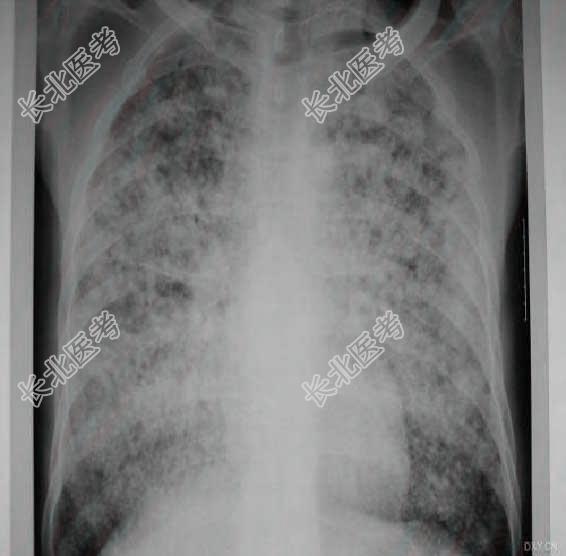

- 多项选择题2.提示:经给予左克.头孢吡肟.去甲万古霉素.氟康唑治疗4天, 仍持续高热,且病情加重出现呼吸衰竭。吸氧3.5L/分条件下, 血气:PH7.49, PaO₂46.8mmHg,PaCO₂7.4mmHg, HCO₃-20.4mmol/L,AaDO₂68.4mmHg。6月6日胸片及CT示双肺弥漫性结节状密度增高影, 内见细支气管充气征,纵膈内有肿大淋巴结。 治疗上应首先采取以下哪些措施

- 多项选择题10.提示:经给予左克.头孢吡肟.去甲万古霉素.氟康唑治疗4天, 仍持续高热,且病情加重出现呼吸衰竭。吸氧3.5L/分条件下, 血气:PH7.49, PaO₂46.8mmHg,PaCO₂7.4mmHg, HCO₃⁻20.4mmol/L,AaDO₂68.4mmHg。6月6日胸片及CT示双肺弥漫性结节状密度增高影, 内见细支气管充气征,纵膈内有肿大淋巴结。如下图。